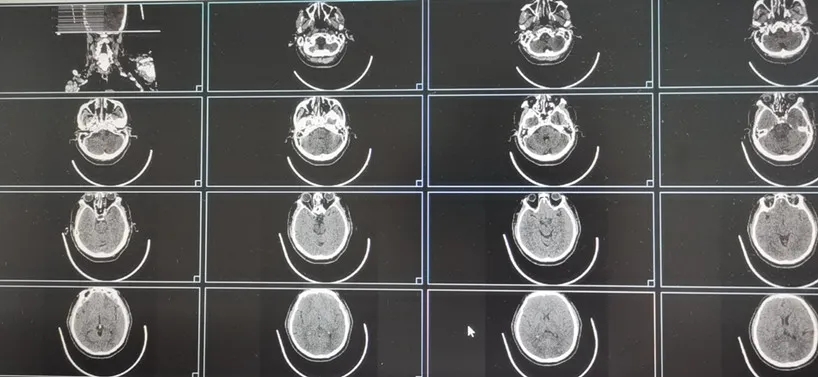

接診的神經(jīng)內(nèi)科周平醫(yī)師快速評估病情后高度懷疑腦血管意外的可能,急診行頭、胸部CT示:急性腦梗死,溶栓刻不容緩!在家屬知情同意后,立即為徐大爺開通綠色通道,阿替普酶(rt-PA)靜脈溶栓治療爭分奪秒地開始了(DNT時(shí)間27分鐘),同時(shí),考慮到患者可能為后循環(huán)大血管的堵塞,在靜脈溶栓的同時(shí)行頭、頸CTA檢查,結(jié)果示基底動(dòng)脈中上段閉塞。

CT影像